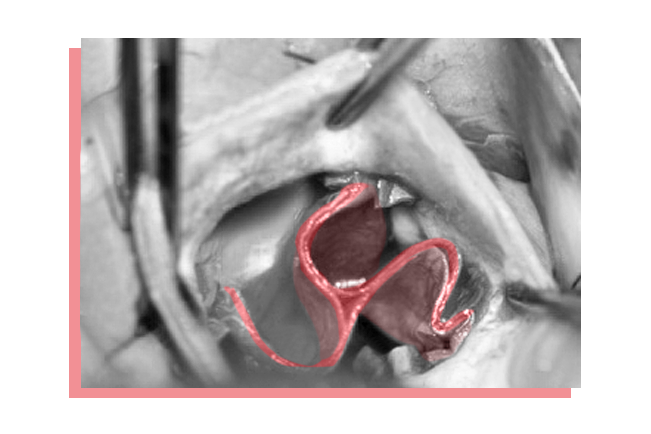

For a few years now, Rüdiger Lange and his surgical team have been crafting completely new heart valves from the body’s own tissue. They do this by cutting a piece from the patient’s own pericardium (heart sac) and using it to make the new valve, which they then insert.

This particularly benefits children and young adults, as it means they no longer need to take medication for the rest of their lives after surgery or receive another new valve a few years later. Only a handful of centers worldwide offer this surgical procedure. In Munich, more than sixty patients have already undergone this type of operation – without any complications to date.